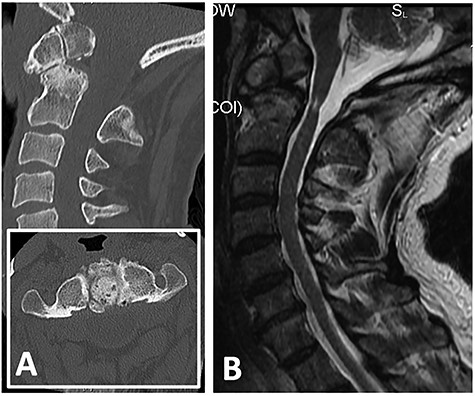

Computed tomography (CT) demonstrated non-union between the odontoid process and body of axis, as well as absence of the posterior arch of atlas (Fig. 1A). Magnetic resonance imaging revealed myelomalacia at the level of non-union likely due to repetitive dynamic compression (Fig. 1B). Flexion–extension X-ray films confirmed significant distraction and forward translation at the atlanto-axial joint (Fig. 2).

(A) CT showing non-union between odontoid process with body of axis (C2) and absence of posterior arch of atlas (C1); (B) T2-weighted MRI revealing cord signal change and atrophy at level of C1/2 suggestive of myelomalacia.